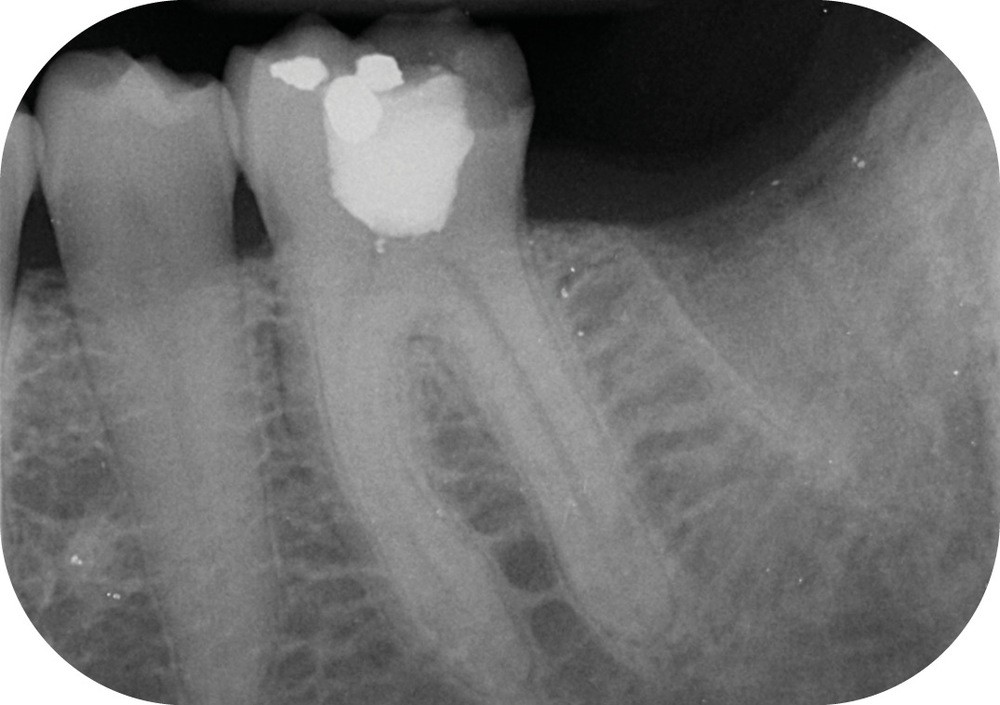

- la nature des alliages. Au début dans leur composition, et plus tard avec des traitements thermiques qui ont permis d’améliorer encore la souplesse lorsque l’évolution des « design » n’était plus possible (fig. 1).

Au moment de la rédaction de ce document, dix-huit systèmes de mise en forme canalaire sont commercialisés sur le marché français. Toutes les publicités promeuvent des améliorations de l’efficacité, de la souplesse et surtout de la résistance à la fracture (fig. 2). Il faut reconnaître que même si ces systèmes sont très différents, les résultats obtenus sont finalement assez constants, et il faudrait des études très poussées pour démontrer la supériorité de l’un par rapport à l’autre (si tant est qu’il y en ait une !).